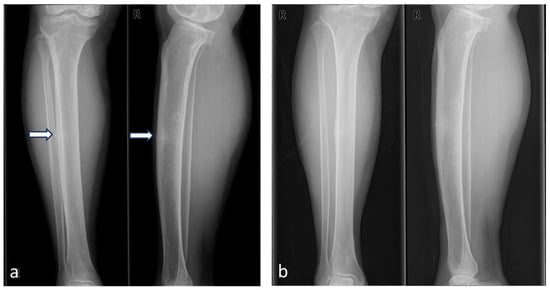

2. Case Presentation